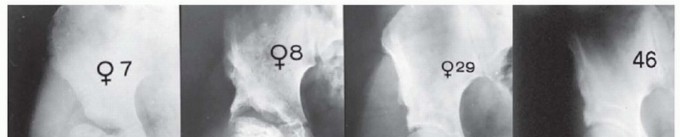

The labral support (shelf) procedure has been used in patients with Legg-Calvé-Perthes disease (or Perthes disease) in Waldenström stages of necrosis or fragmentation in which the femoral head shows deformity or is at risk for deformity6, 12 (

FIG 1

).

FIG 1 • Anteroposterior (AP) radiograph of an arthrogram demonstrates a labral support (shelf) in a patient with Perthes disease. The shelf supports the labrum and enlarges the acetabulum to prevent subluxation of the femoral epiphysis.